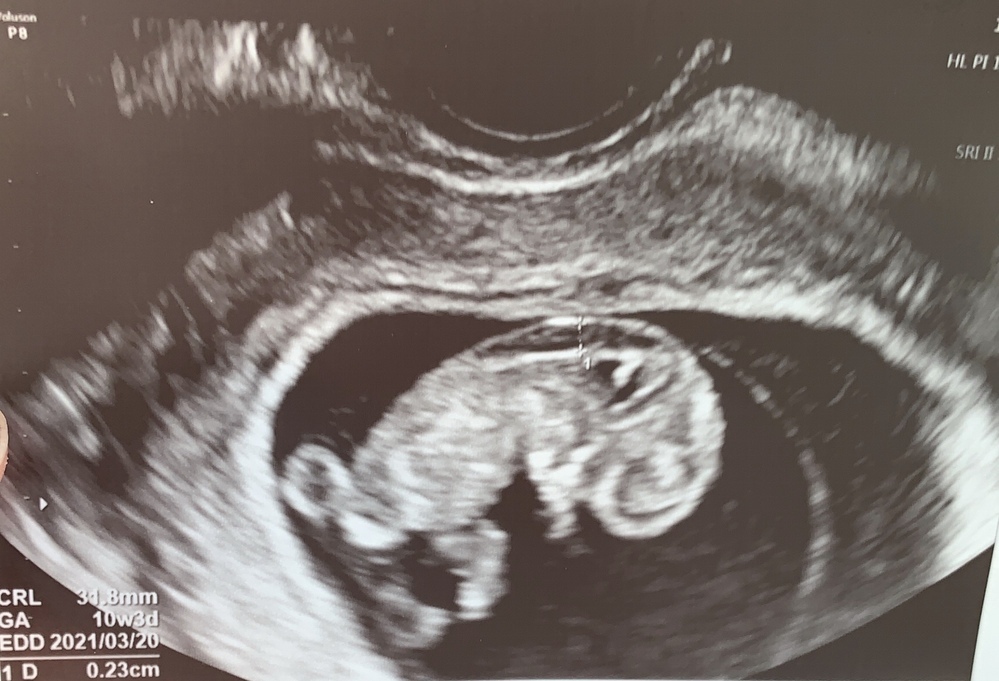

妊娠9週 エコー写真

妊娠9週 エコー写真- 9週0日(9w0d・女の子)|このたんママ さん(23歳) エコー写真撮影時のエピソード: 妊娠が分かり初めて産院にかかった際のエコー写真です! 妊娠に気づくのが遅かったのか、もう既に小さいけども人間の形をしていてびっくりと共に、かわいくて思わず笑顔になってしまいまし 妊娠4〜7週頃 妊娠初期はまだ赤ちゃんが小さく、膣から超音波(エコー)検査を行うことが多いです。 一番最初にエコーで確認できるものは胎嚢(gs)です。妊娠4〜5週頃に子宮の中に小さい黒い丸として映ります。 次に見えてくるのは卵黄嚢です。

妊娠中の「エコー写真」と 「当時の様子」を記録しています わたしにとって二回目のエコーの様子です。 この日に産院で「妊娠届出書」を貰いました! 目次(読みたい項目にジャンプ出来ます) 妊娠9週目 赤ちゃんの様子 妊娠9週目 妊婦(わたし)の美月です🌙 ホルモンを分泌する脳下垂体の前葉が生まれつきない27歳です。 昨日で不妊治療のクリニックを無事に卒業したので、今日は振り返りの記事です 毎週診てもらっていたので 「もう1週ごとの成長を見れないのか」 と思うとちょっと悲しく 妊娠9週2日目のエコー写真と、赤ちゃんの大きさについてを書いていきます。 妊娠9週、毎日1日10回くらい吐いてた私なんですが、2日前から悪阻がマシになっています。 目次 9w2dのエコー写真。 赤ちゃんの大きさのCRLは217mmです。 妊娠9週で

ねんれい 31 妊娠週 9w5d 9w5d、初の妊婦健診で撮ってもらった経膣エコー。 こんなにハッキリと、お人形のようにまん丸な手足が写ってとても嬉しかった。 出産経験のある友達にも、ここまでハッキリしたエコーはなかなか無いかも!と言われて嬉しかった妊娠週 9w2d 結婚して9年、不妊治療5年。 昨年初めての妊娠は7週で稽留流産となり、今回の妊娠は嬉しさと同時に不安も多く、毎回エコーで赤ちゃんの成長を実感するまでドキドキです。 9週目の赤ちゃんは219mm、二頭身でクネクネと元気に動いていました